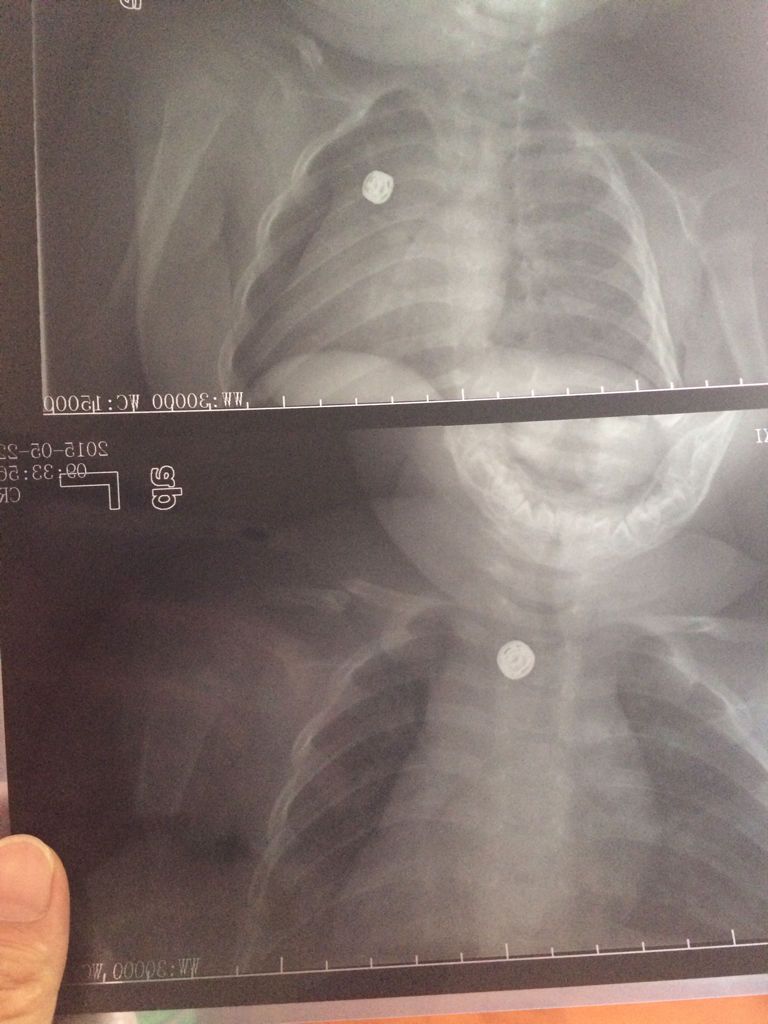

6个月宝宝左锁骨骨折,缠了八字绷带第二天左脸肿了怎么 点击展开 匿名用户 2015-05-23 11:47 为您推荐: 其他回答 考虑是绑带绑得太紧了导致颜面部的静脉回流无法回到心脏去的缘故,建议如果肿胀厉害需要返院适当的松一些绑带 笑天下美女 2015-05-23 12:35 相关问题 6个月宝宝从床上摔地上了,左侧朝下,左锁骨骨折了,医生缠了绷带,第二天左脸上 新生儿锁骨骨折错位了,当时拍片是发现,后来医生接了,还打了绷带,现在已经两周了,到医院复查后发现断 你好,我家宝宝17个月大了,锁骨骨折给她绑了8字绷带,绑了